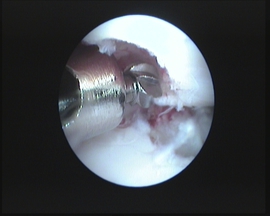

Dirigido y fundado por Alfonso Chico, las 10 personas que componen su plantilla tienen como prioridad mejorar la salud de sus pacientes combinando un trato humano y personalizado con técnicas y equipos de vanguardia. Esto hace del CQV un referente a nivel nacional en el tratamiento de patologías como la displasia de codo, lesiones de rodilla o enfermedades articulares. Por esta razón, diversas empresas y laboratorios buscan frecuentemente su colaboración para estudios clínicos y lanzamiento de productos, y nuestra presencia como ponentes es requerida en numerosos congresos.

- Traumatología y ortopedia. Artroscopia